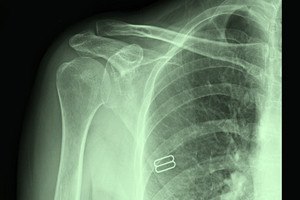

כל אחד עלול לסבול מפריקת כתף: ספורטאים, רוכבי אופנוע, אנשים בעלי גמישות יתר או "סתם" אדם שנחבל. מתי ניתן לקבע את הכתף ללא ניתוח ומתי יש צורך בניתוח?